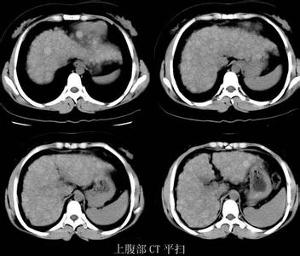

檢查

5、肝臟B超檢查,了解肝臟的組織結構及肝臟血管構造情況。